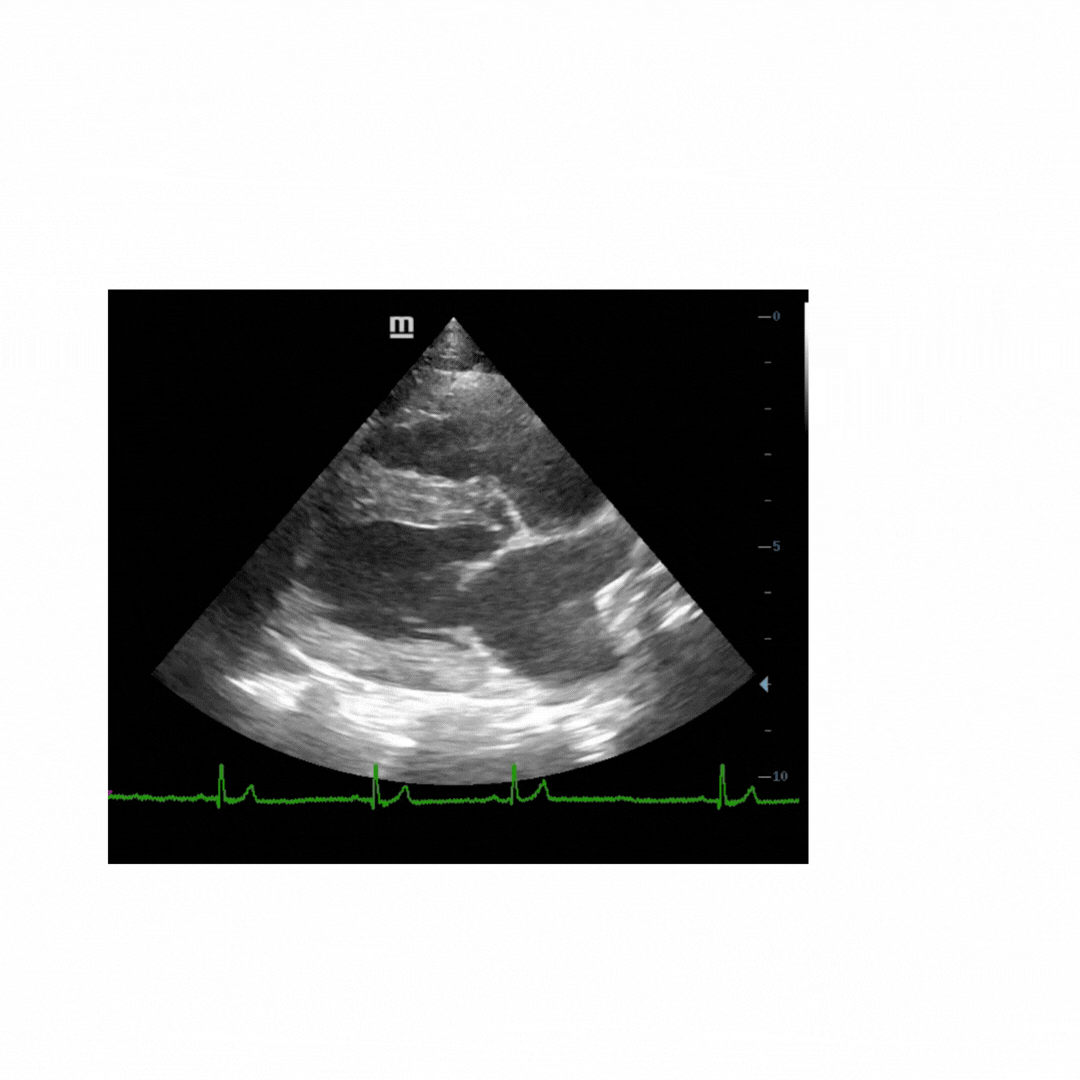

Emergency ultrasonography and diagnostic imaging

Videos and annotated images show you how to perform point of care ultrasonography including focused cardiac ultrasound. What’s normal? What’s abnormal? - This section will show you.

Abdominal ultrasonography and radiographs will help you make sense of your diagnostic imaging.